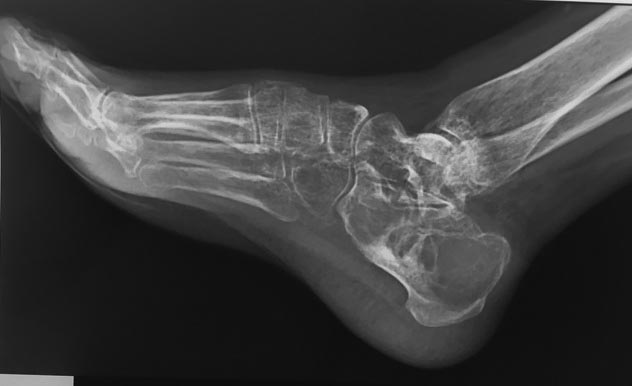

Пациентка с большой аневризмальной костной кистой пяточной кости.

Пациентка Г., 38 лет. 1,5 года назад появились боли в левой пяточной

кости. Болей в покое и ночных болей нет. 08.09.15 операция: экскохлаеция

аневризмальной костной кисты, пластика деминерализованными костными

трансплантатами. По данным МРТ (29.02.16) костной

перестройки нет, вероятно произошел выход содержимого кисты в

пространство позади ахиллова сухожилия.

Планируется проведение РКТ, биопсии. Вопрос: чем можно заполнить ?

Костный цемент? Или снова деминерализованные костные трансплантаты?